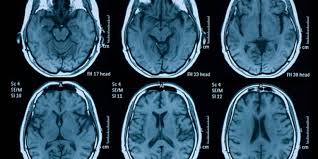

O Acidente Vascular Cerebral (AVC) continua sendo uma grande preocupação no Brasil. As informações mais recentes confirmam que a doença ainda é responsável por uma morte no país a cada poucos minutos. A relevância desses dados está no fato de que a grande maioria dos casos, cerca de 80%, poderia ser prevenida. O foco está na importância de controlar fatores de risco como hipertensão, diabetes, colesterol e tabagismo, além de adotar hábitos de vida saudáveis, para reduzir significativamente a incidência e o impacto dessa condição.